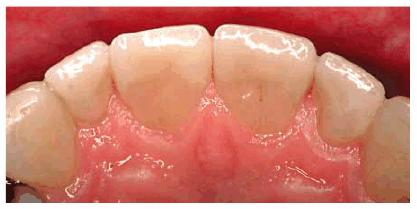

Figure 24-2A: This patient was dissatisfied with her crowded anterior teeth. Note how the gingival height differs between the central and lateral incisors.

Figure 24-2B: The dissimilar gingival heights did not bother the patient because her natural smile line concealed these irregularities.

Figure

24-2C: After a slight reproportioning of the six anterior teeth, direct

composite resin was placed and contoured (6-mm ET [Brasseler,

Figure 24-2D: The final result shows improved proportion in tooth size and form.